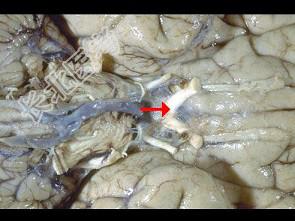

- 单项选择题如图箭头所示为视觉系统哪个部位 ( )

A、视束

B、视交叉

C、视不变

D、视乳头

E、视神经